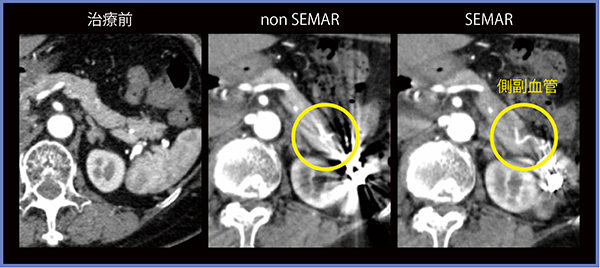

脾動脈瘤に対しpackingとisolationを行った症例では,治療後のnon SEMARの画像では周囲の状況の把握は困難であるが,SEMARを用いることでアーチファクトに隠れていた側副血行路が確認できた(図6)。

図6 脾動脈瘤に対してpackingとisolationを行った症例(70歳代,男性)